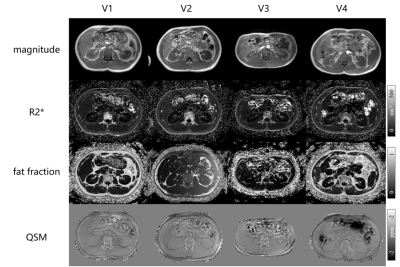

The magnitude image, R2* map, fat fraction and QSM maps of the four volunteers are shown in Fig. 3.

Fig.3. Magnitude images, R2* maps, fat fraction and QSM maps of four volunteers.